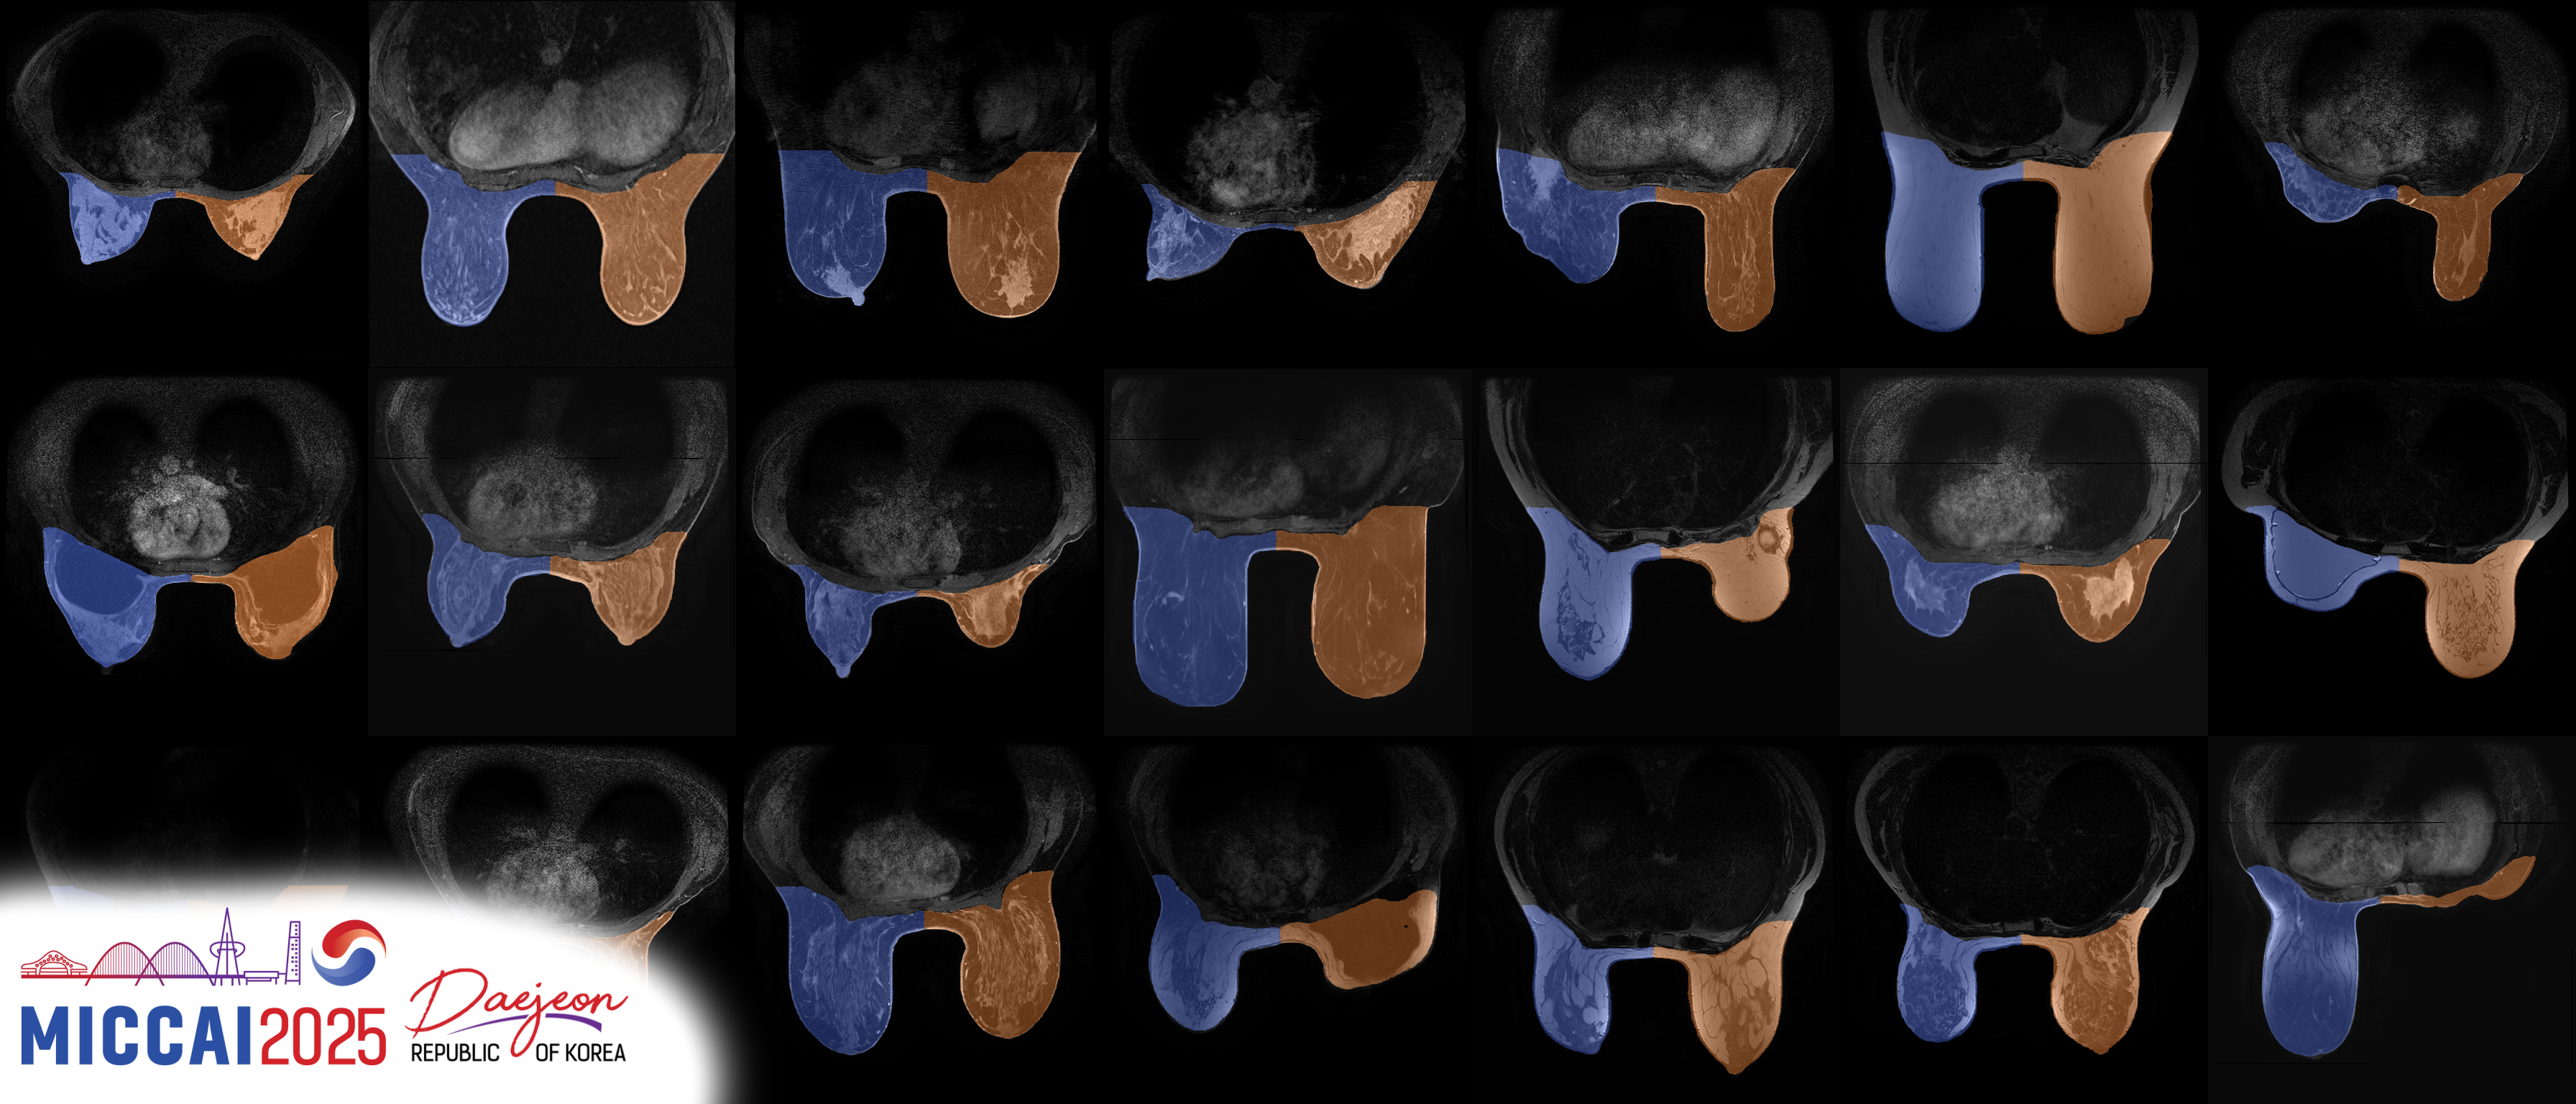

Breast MRI plays a pivotal role in breast cancer detection, diagnosis, and treatment planning. BreastDivider addresses a critical limitation in breast MRI segmentation: the lack of distinction between the left and right breasts in most public datasets and models.

In this work, we introduce the first publicly available large-scale dataset with explicit left and right breast segmentation labels, comprising over 13,000 3D MRI scans. Accompanying this dataset is a robust nnU-Net–based segmentation model, trained specifically to identify and separate left and right breast regions in clinical MRI data. This effort provides a foundation for developing high-quality, anatomically aware tools for breast MRI analysis and offers opportunities for large-scale pretraining.

The model is based on the nnU-Net framework and was trained on the full BreastDivider dataset, using a custom configuration that allows both breasts to fit into a single 3D patch.

It generalizes well across a variety of MRI modalities, including: